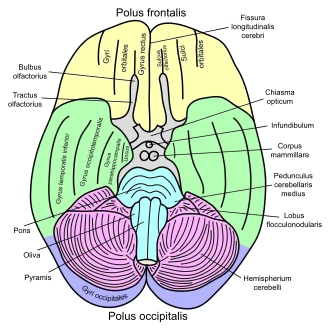

Basal view of a human brain

Basal view of a human brain